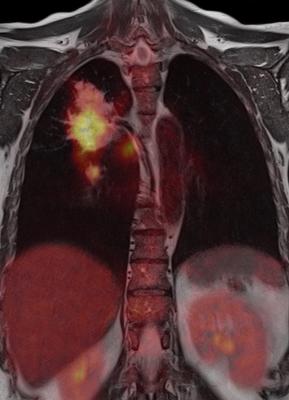

As part of the collaboration, medical imaging data from the AIR study - a French, multicenter cohort study, led by the Nice Hospital that has enrolled, to-date, more than 600 high-risk patients (smokers or former smokers with Chronic Obstructive Pulmonary Disease [COPD]) screened for lung cancer - will be analyzed to identify and characterize pulmonary nodules visible in thoracic CT scans. By using Deep Learning methods, a discipline of Artificial Intelligence, Median will develop new algorithms to identify imaging biomarkers that indicate pulmonary nodule malignity.

While current CT scan performance enables more pulmonary abnormalities to be identified, post-treatment image applications do not allow for an automatic, accurate characterization of the malignity or benignity of these pulmonary abnormalities. Lung nodule biopsies, which are invasive, are needed to confirm a diagnosis - potentially leading to complications for patients. By using medical imaging biomarkers, clinicians can reduce unnecessary biopsies and more accurately diagnose patients.

"Early detection of lung cancer is of paramount importance if we want to lessen mortality of this disease", says Professor Charles Marquette, coordinator of clinical teams in the AIR study. "The rationale for screening is based on the tight relationship between outcome and extent of the disease at time of diagnosis. However, large-scale screening of unselected population with chest computed tomography (CT) is expensive and has a high harm to benefit ratio, which explains why many health agencies are reluctant to implement screening of lung cancer with chest CT alone. We are developing a multimodal approach to lung cancer screening, including refinement of screening criteria (e.g. focus on COPD), non-invasive biomarkers and use of Artificial Intelligence to better characterize chest CT findings.”

"Today, many pulmonary biopsies are performed unnecessarily; Artificial Intelligence is going to make imaging, which represents non-invasive and less expensive procedures, an improved therapeutic decision-making tool. With Artificial Intelligence, imaging will help to identify patients who really need a biopsy and will contribute to advance clinical practice," said Peter Bannister, Chief Technology Officer at Median Technologies.